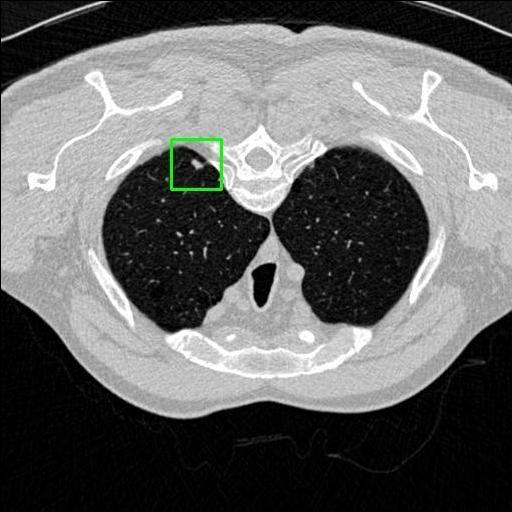

We developed an AI-based system using deep learning models for analyzing lung CT scans to detect and classify pulmonary nodules. We chose the YOLOv11 architecture for its enhanced object detection capability and adapted it specifically for medical imaging, incorporating pixel-level precision and severity classification.

Classification into three severity levels with colored bounding boxes.

Medical image characteristics (non-RGB, soft tissue contrast) made general-purpose models less effective without fine-tuning.

Designed a severity classification system that categorizes nodules into null, moderate, and severe using colored bounding boxes, assisting in rapid clinical decision-making.